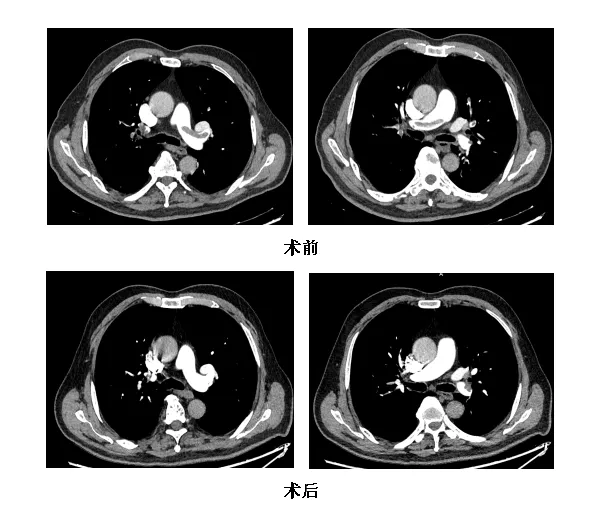

危急关头,湖北省第三人民医院呼吸疾病诊疗中心高宝安主任团队紧急集结,为他实施了急诊肺动脉造影+抽吸取栓术。将导管导管精准送至肺动脉血栓部位,借助负压抽吸系统成功抽吸出血栓。术后造影显示,肺动脉主干及分支血流恢复,血氧稳定。肖爹爹激动地说:“终于不闷了,  我好了!